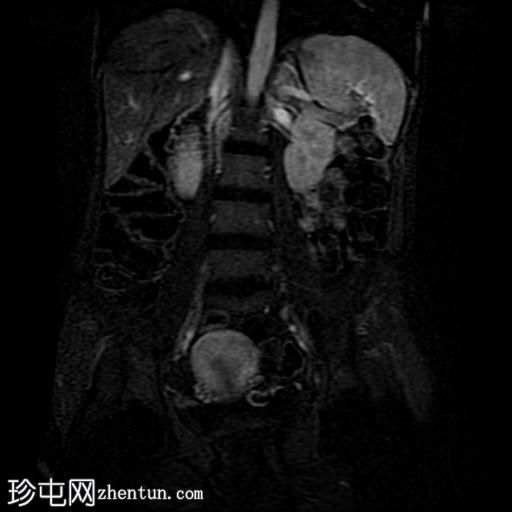

冠状位T2加权像

脂肪抑制

轴位

T2加权像

轴位T1加权像

增强脂肪抑制

冠状位T1加权像

回肠末端及盆腔回肠肠袢可见长段肠壁增厚及强化,肠周血管丰富,呈“梳状征”,并可见明显的纤维脂肪浸润。

未见瘘管、积液、腹水或梗阻。

磁共振肠道造影(MRE)结果支持克罗恩病的诊断,显示远端及末端回肠以活动

性病

变为主,并可见明显的肠周血管。